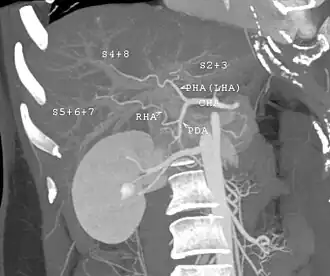

The vast majority of liver transplants use the entire liver from a non-living donor for the transplant, particularly for adult recipients. A major advance in pediatric liver transplantation was the development of reduced-size liver transplantation, in which a portion of an adult liver is used for an infant or small child. Further developments in this area included split liver transplantation, in which one liver is used for transplants for two recipients, and living donor liver transplantation, in which a portion of a healthy person's liver is removed and used as the allograft. Living donor liver transplantation for pediatric recipients involves removal of approximately 20% of the liver (Couinaud segments 2 and 3).

In a typical adult recipient LDLT, 55 to 70% of the liver (the right lobe) is removed from a healthy living donor. The donor's liver will regenerate, approaching 100% function within 4–6 weeks, and will almost reach full volumetric size with recapitulation of the normal structure soon thereafter. It may be possible to remove up to 70% of the liver from a healthy living donor without harm in most cases. The transplanted portion will reach full function and the appropriate size in the recipient as well, although it will take longer than for the donor.[17]

- Before one becomes a living donor, the donor must undergo testing to ensure that the individual is physically fit, in excellent health, and does not have uncontrolled high blood pressure, liver disease, diabetes, or heart disease.[19] Sometimes CT scans or MRIs are done to image the liver. In most cases, the workup is done in 2–3 weeks.